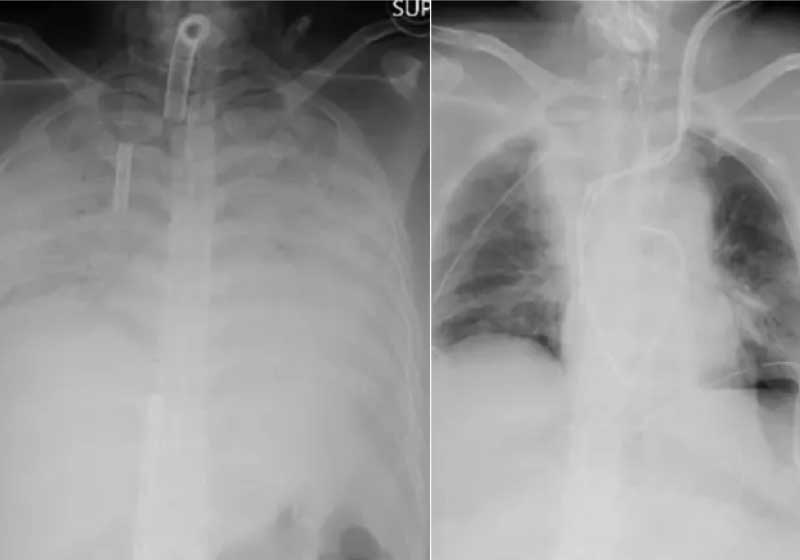

As complicações levaram a paciente a ficar por meses em uma máquina que funcionava como um pulmão artificial, de acordo com o Hospital da Universidade de Kyoto.

A covid deixou sequelas fortes no pulmão da mulher, a ponto de o órgão não funcionar mais sem apoio de um aparelho.